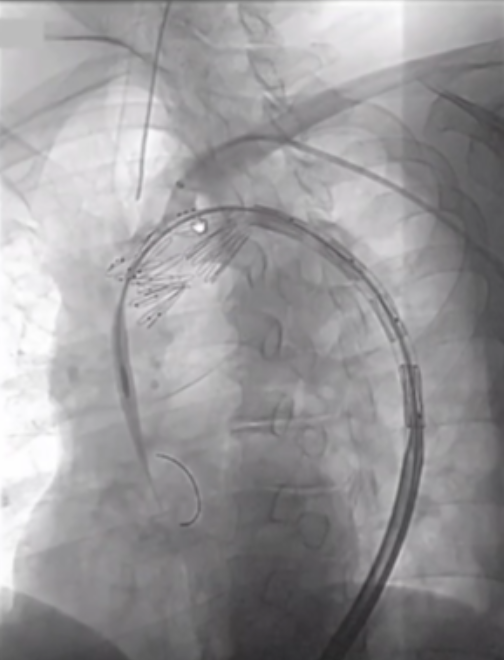

在近端密封区选择上,通常需向近端延伸25-30mm以实现更优密封效果,而定制器械凭借开窗设计,能有效增加密封长度。定制化支架技术也至关重要,支架必须精准定位,标记移动易引发开窗错位;同时要做好旋转控制,否则支架旋转不良会提升逆行夹层风险。一旦出现开窗对齐问题,可能导致I型内漏,且长期处理难度大,需借助更复杂的穿通技术纠正分支位置。

在主动脉介入治疗领域,支架设计持续创新。Terumo双分支支架采用大型矩形凹槽设计,即便旋转90度,仍能顺利接入分支,对于弓部曲线较为紧张的情况适配性更强。不过,该支架也面临技术挑战,手术中需要精准控制支架的旋转与对齐,以确保治疗效果。

深圳设计的支架同样亮点十足。它具有短输送尖端的特点,无需跨越主动脉瓣,部署过程简单,且不需要进行严格的血压控制。支架配备两个平行侧支,搭配低剖面8-9F桥接支架,在接入方式上,采用右臂入路结合左颈动脉小切口的方式,为手术操作提供了便利,也有望为患者带来更优的治疗体验。